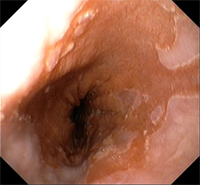

Esófago de Barrett

Esófago de BarrettEl esófago de Barrett es una alteración de la mucosa de esófago que, como consecuencia del reflujo gastroesofágico persistente, se inflama tanto que incluso llega a cambiar de características histológicas. Este cambio de tejido es la única característica que nos permitirá hacer el diagnóstico, es decir, el diagnóstico de esófago de Barrett no se puede establecer por el aspecto de la mucosa en la endoscopia ni por los síntomas del paciente ni por la demostración de un exceso de ácido refluido. Lo único que nos da el diagnóstico es demostrar que en el esófago se encuentra tejido de tipo intestinal (lo que se conoce como metaplasia intestinal) y si no hay tejido de estas características no se puede hacer el diagnóstico de esófago de Barrett.